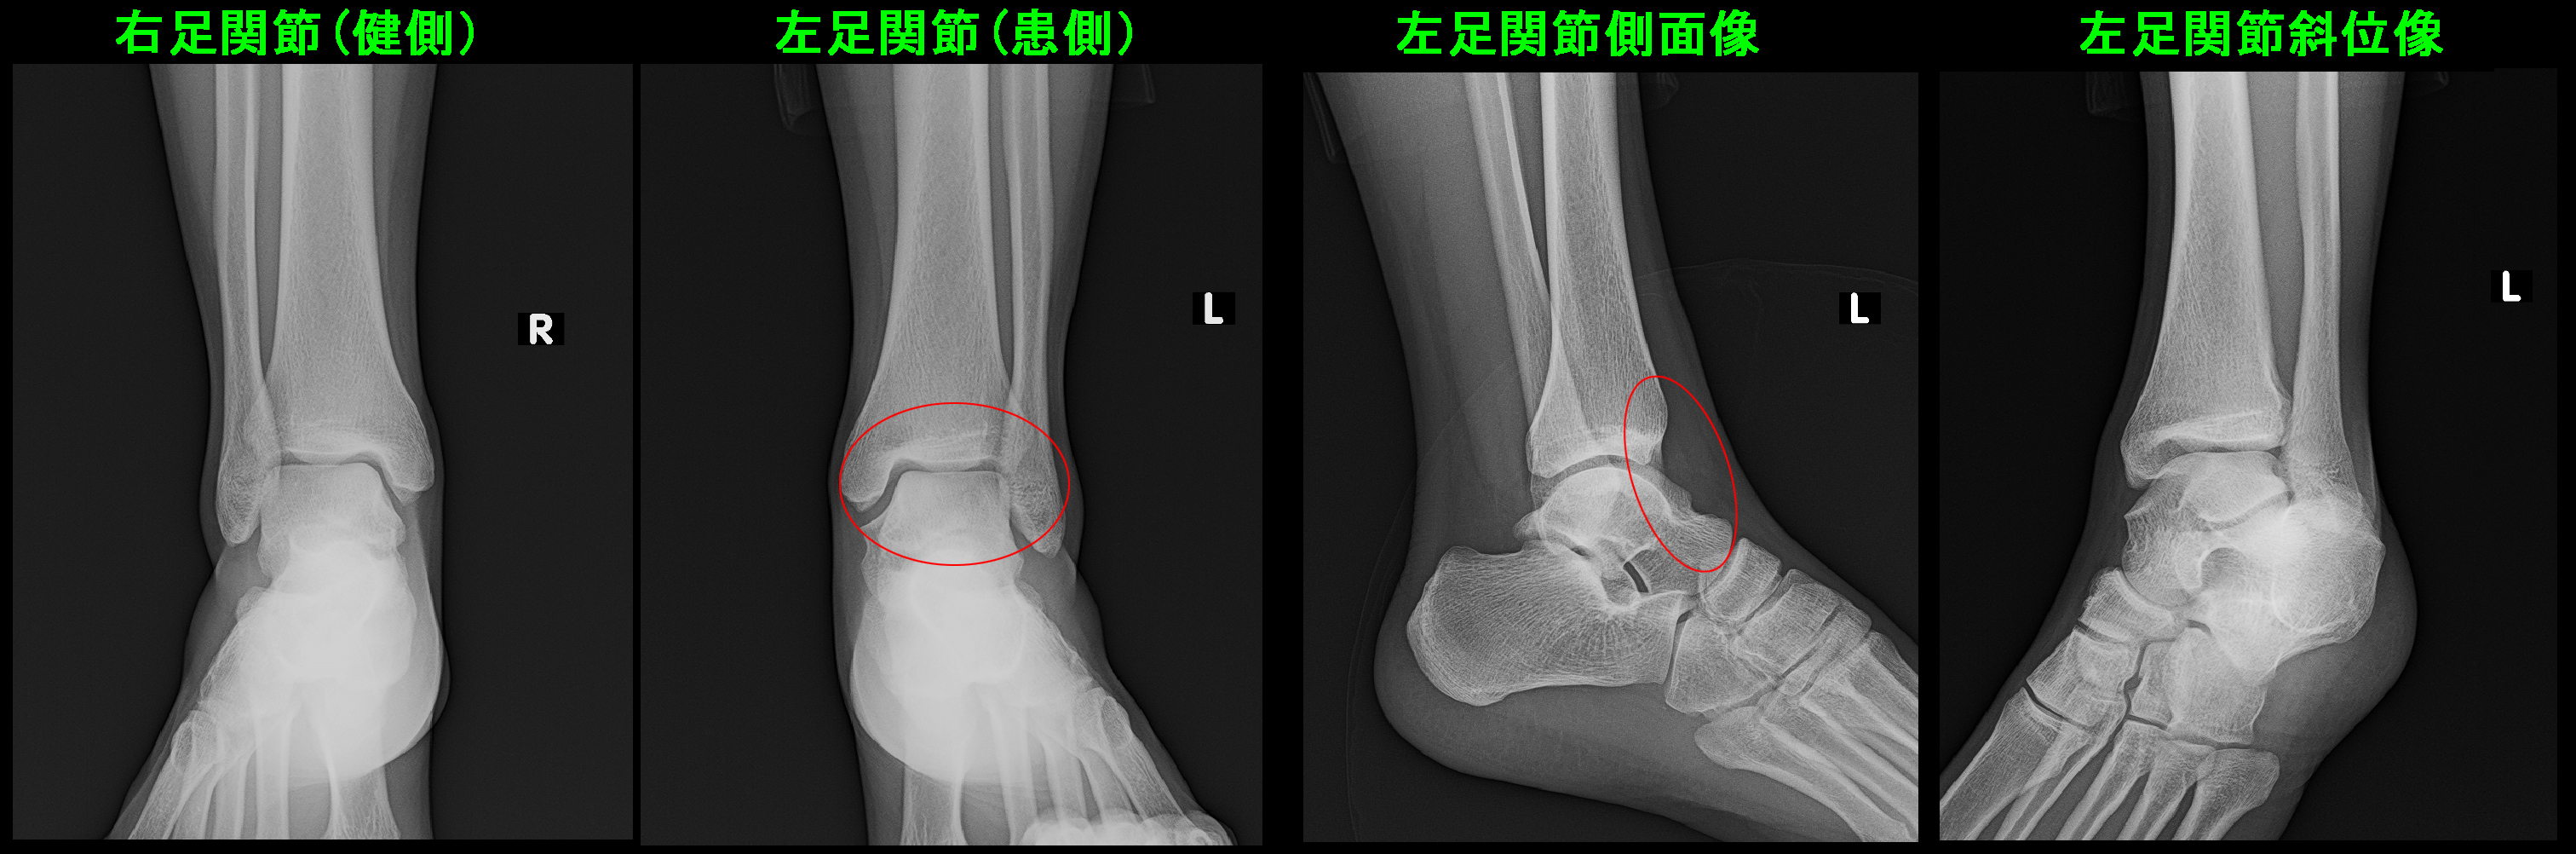

下図の患者さんは22才の男性で、X年2月にスノーボードで左足関節を捻挫し、他整形外科を受診したが異常なしとされ、シップの処方のみを受けたそうです。

同年10月28日,、受傷から8か月経過して当院を受診されましたが、受診時まで立ち上がりや歩行、階段昇降では痛みはなく、スポーツ時には痛みはVAS6~8で(VASスケールについては部位別診療例の”痛みについて”を参照のこと)、びっこ(左足をひきずる歩行)となってしまう状態が続いているという相談でした。

捻挫受傷時も経過中も左足関節の腫脹はなかったと述べていました。

受診時にも左足関節には腫脹はなく、レントゲン像では異常は確認されません。おそらくこの問診で診断が想起できる整形外科医はいないのではないかと私は思います。

上図のSTIR条件のMRI画像では患側の左足関節の距骨という骨が白くなっています。これは骨内の出血と同様の所見で疲労骨折と評価して良い所見です。

また距骨の足関節面はきれいな円形でなくなっています。これは疲労骨折により劣化した距骨に体重負荷がかかり続けて円形の関節面が変形したものと理解されます。